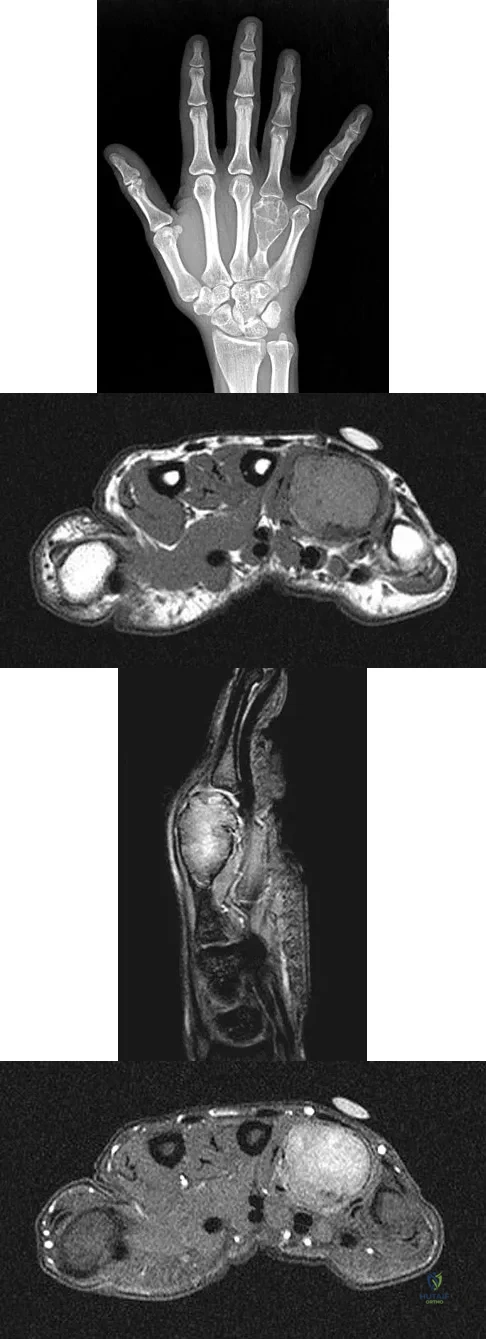

A 26-year-old man has had hand pain and progressive swelling in the knuckle for the past several months. He denies any trauma to the hand. The ring finger metacarpophalangeal joint is tender, and there is loss of motion in the digit. Figure 32a shows the radiograph and Figures 32b through 32d show the T1-weighted, T2-weighted, and gadolinium MRI scans, respectively. What is the most likely diagnosis?

Explanation:

The radiograph reveals a subchondral lesion in the metacarpophalangeal joint that is lytic and expansile. The MRI scans show a mass that is moderate in intensity on the T2-weighted image and has some gadolinium uptake. There are no cystic components in this lesion. The subchondral location and expansile nature are highly suggestive of giant cell tumor of bone. A lesion with this appearance might also represent an aneurysmal bone cyst, given the amount of expansion present. Menendez LR (ed): Orthopaedic Knowledge Update: Musculoskeletal Tumors. Rosemont, IL, American Academy of Orthopaedic Surgeons, 2002, pp 113-118.